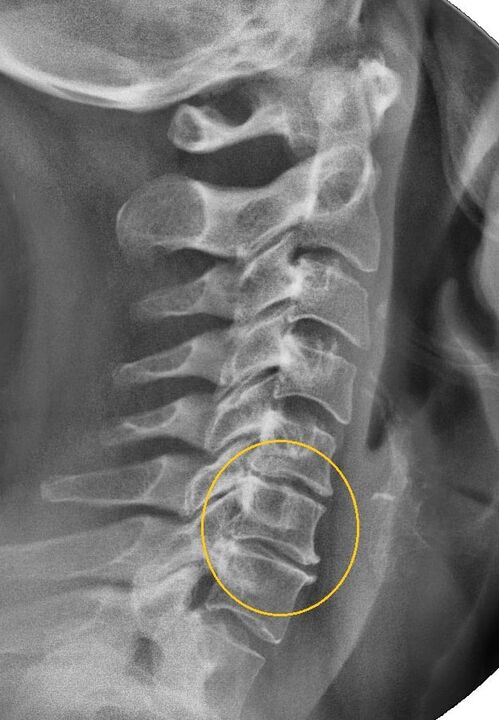

Rentgens – parāda, kādā stadijā slimība, ja ir kaula struktūras izmaiņas – artroze. Var pasūtīt arī MRI un CT skenēšanu.